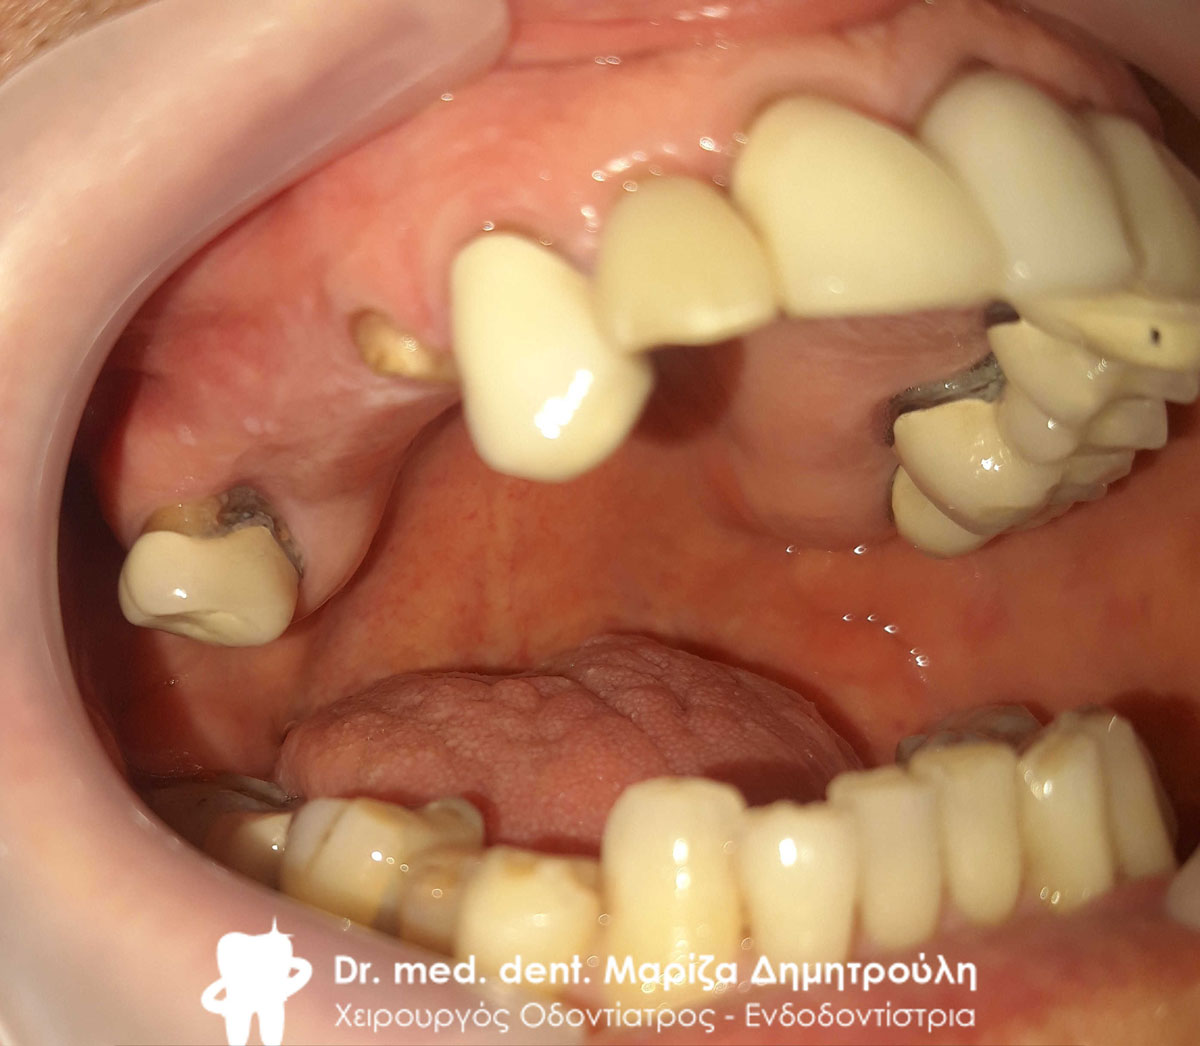

Αρχική κλινική εικόνα της άνω γνάθου

Αρχική κλινική εικόνα της αριστερής πλευράς της άνω γνάθου

Αρχική κλινική εικόνα της δεξιάς πλευράς της άνω γνάθου

Αρχική κλινική εικόνα της υπερώιας πλευράς της άνω γνάθου

Αρχική κλινική εικόνα της υπερώιας πλευράς της άνω γνάθου

Αρχική κλινική εικόνα του στόματος του ασθενή